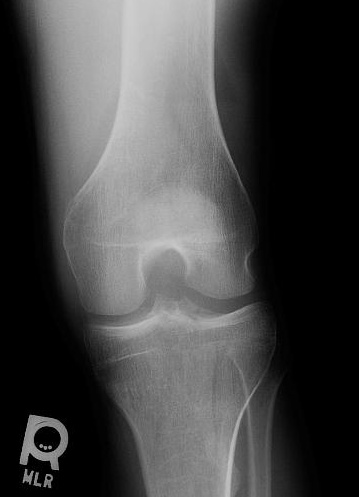

KNEE - OBLIQUE RADIOGRAPH

This oblique radiograph demonstrates the lateral tibial fracture to better advantage, but the lipohemarthrosis is not visible.